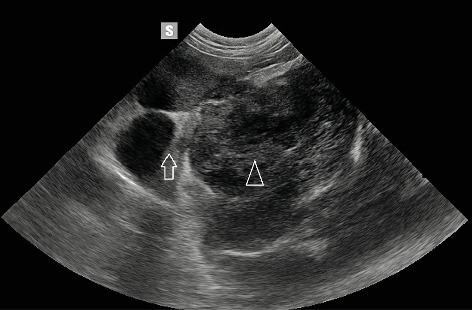

A dog (neutered male, 11 years old, Labrador retriever) underwent abdominal ultrasound, which revealed a 7 cm diameter tumour (caudal region of the left kidney). The animal showed symptoms of weight loss, apathy, haematuria, and abdominal pain. A computed tomography (CT) scan confirmed the presence of a tumour originating from the ureter. Following surgery to remove the ureter with the attached kidney, a histopathological examination was performed. The tumour was classified as a haemangiosarcoma. After the initial recovery, 2 months after surgery, the dog was diagnosed with a tumour in the other kidney. A fine needle biopsy was carried out. A haemangiosarcoma metastasis was suspected. Neoplasms of the ureter are a rare pathology. This is the first case in which metastasis to the second kidney has been confirmed.